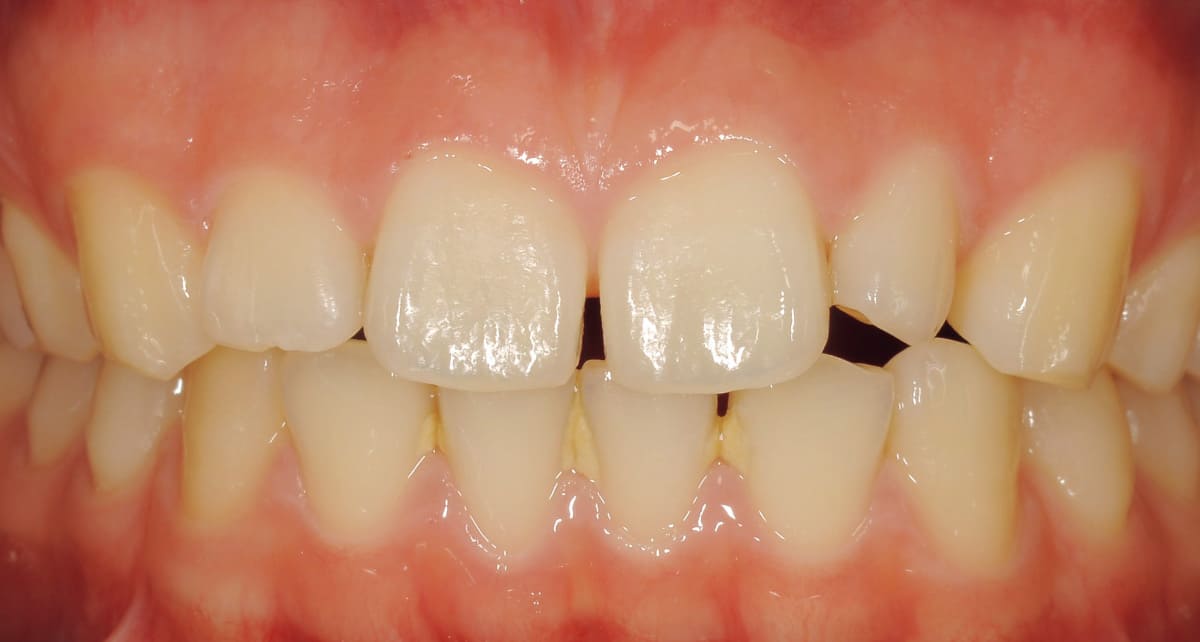

ラミネートベニア|イメージはネイルチップ。前歯のトラブルを改善。

Before

After

歯の表面のエナメル質を薄く削り、薄い板状のセラミックを直接貼り付ける治療法。歯の色や形、すきっ歯などの改善に対応する。いわゆる付け爪のイメージで治療は短期間、歯への負担も少ない。前歯の処置に用いられることが多い。

【料金】10万円〜

【治療期間】1週間〜3週間程度